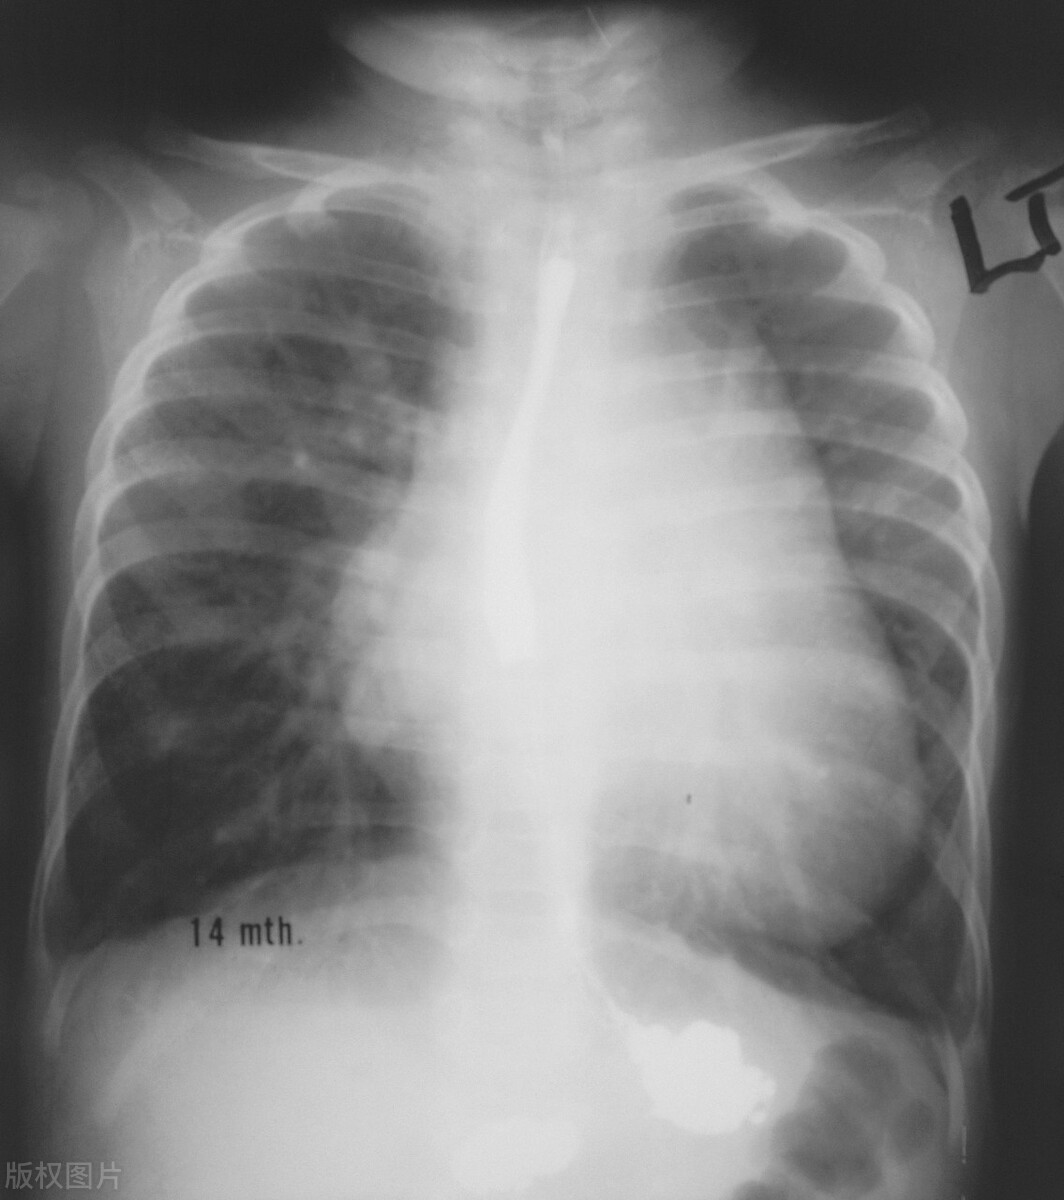

肺心病的诊断是基于彻底的病史、体格检查和实验室检查。胸部X光片、心电图和超声心动图可以帮助诊断病情。肺心病的治疗取决于根本原因,可能涉及药物、氧疗和生活方式的改变。在某些情况下,可能需要手术来治疗潜在的肺部疾病。